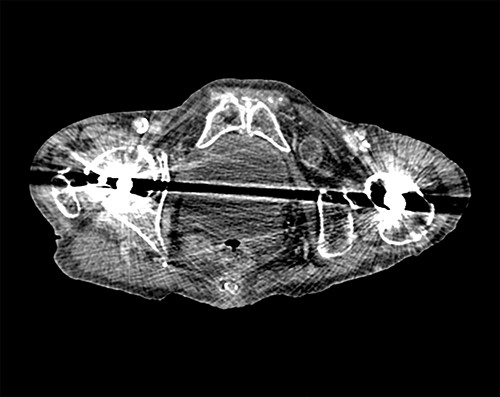

Following surgical review, a computerized tomography (CT) scan of the abdomen and pelvis was requested and showed small bowel obstruction, secondary to a left-sided obturator hernia (Figs 1 and 2).

Axial view of CT scan showing the bowel loop through the left obturator hernia.